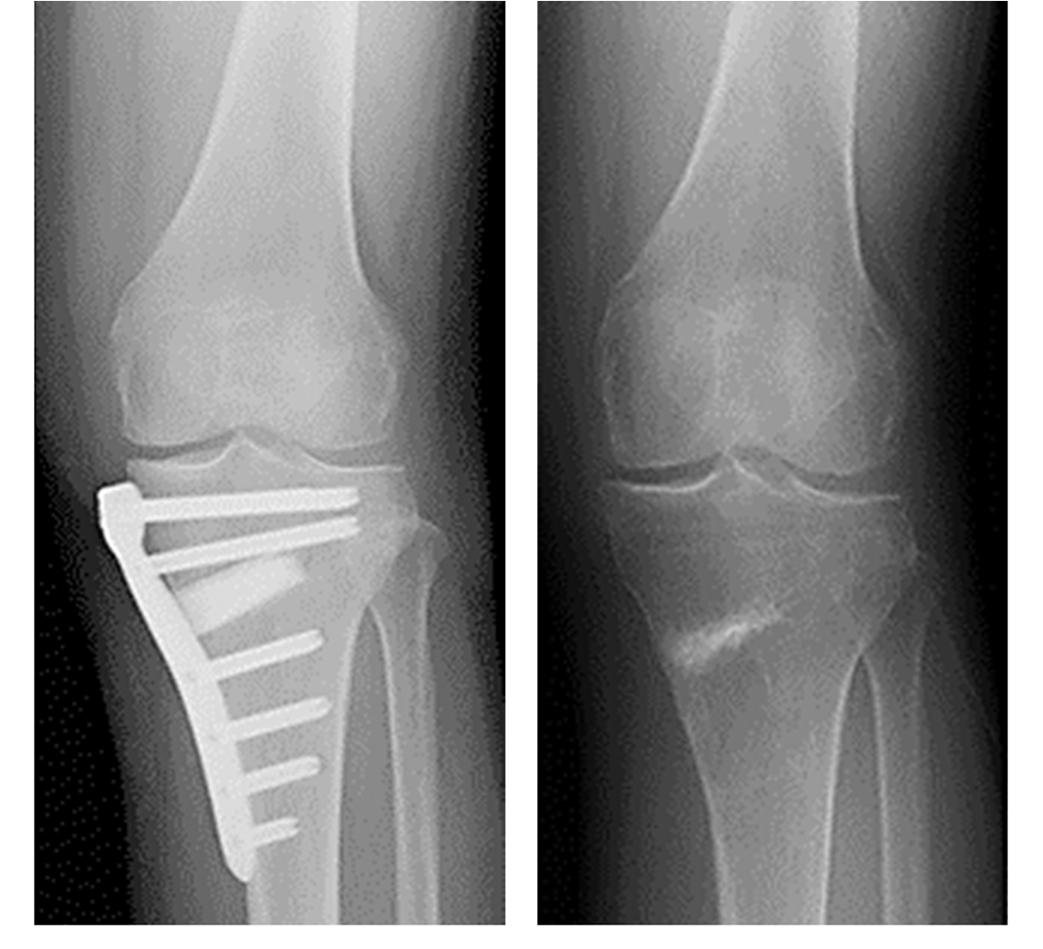

骨きり術の中でも、Opening Wedge法を採用しています。骨きり術とは、脛骨(すねの骨)の一部分に切れ目を入れて、間を広げ、O脚となっている脚を軽いX脚に矯正した状態でプレートで固定する手術です。体重のかかる軸を内側から外側に移動させることで痛みが取れ、また傷んだ軟骨も再生することが知られています。人工関節と異なり、“関節温存手術”と言われ、関節の機能が温存できる、低侵襲で合併症が少ない、良好な可動域(ひざを深く曲げることが可能)、スポーツなどに制限がない、などのメリットがあり若年者や比較的軟骨の残っている場合に行われます。 デメリットとしては、切った骨が治る(骨癒合)までに時間がかかり、リハビリ・社会復帰にやや時間を要することです。

HTOの術後レントゲン